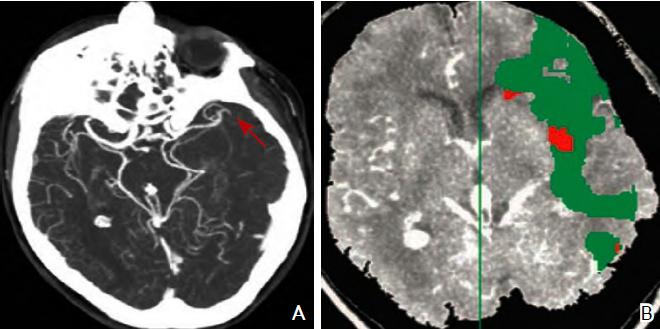

CT灌注成像针对梗死核心灶标记为CBV降低的区域,CBF与MT T以低于界定的阈值(CBV<2 ml/100 g、CBF<20 ml/100 g/min及MTT>8 s)来显示脑的异常灌注区。缺血半暗带为脑梗死核心区与异常灌注区域之间的差异区域(图3)。

图3 CT血管造影(A)及CT灌注成像(B)注:A:CT血管造影显示大脑中动脉闭塞(红色箭头所示);B:CT灌注成像,绿色区域为平均通过时间(MTT)异常区域(MTT 145%,与对侧正常比较),红色区域为脑血容量(CBV)降低区域(CBV<2.0 ml/100 g)。CT:计算机断层扫描